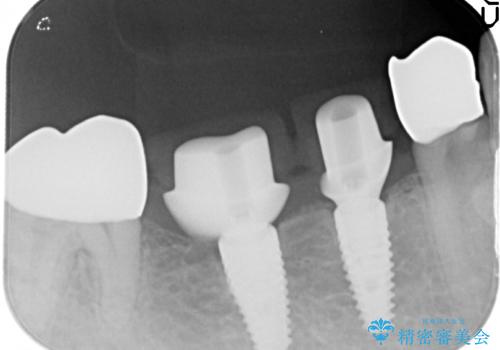

設計に無理のある長期的に良好な状態が保てるとは思えないブリッジを除去し、インプラントを用いた補綴計画を立てます。

ブリッジは欠損部位の距離が長くなればなるほど支台となる歯の負担がまし、大きな咬合力負担による外傷や破折など大きなリスクにさらされます。

インプラントを用いることで残っている歯の負担も減らし、長期的な予後を見込むことができます。